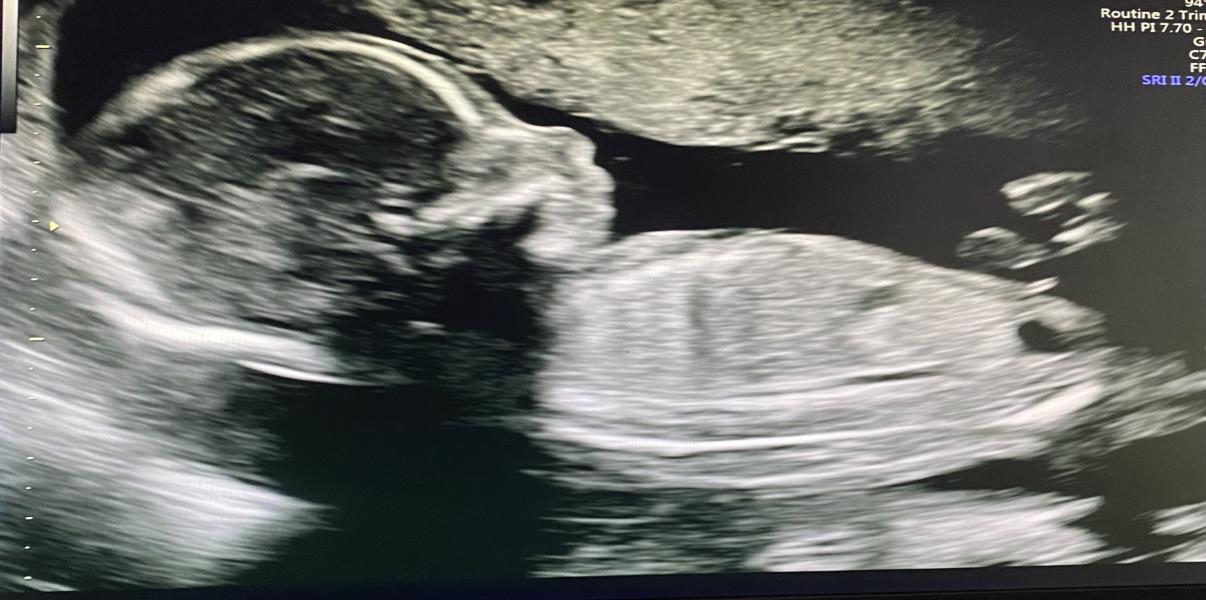

Сегодня сходила на второй скрининг, очень классная врач-узист мне попалась, все объясняла, ответила на вопросы

Подтвердили пол, моя принцесса ничего не отрастила за месяц 😄

Малышка развивается отлично, никаких отклонений, все показатели прекрасны